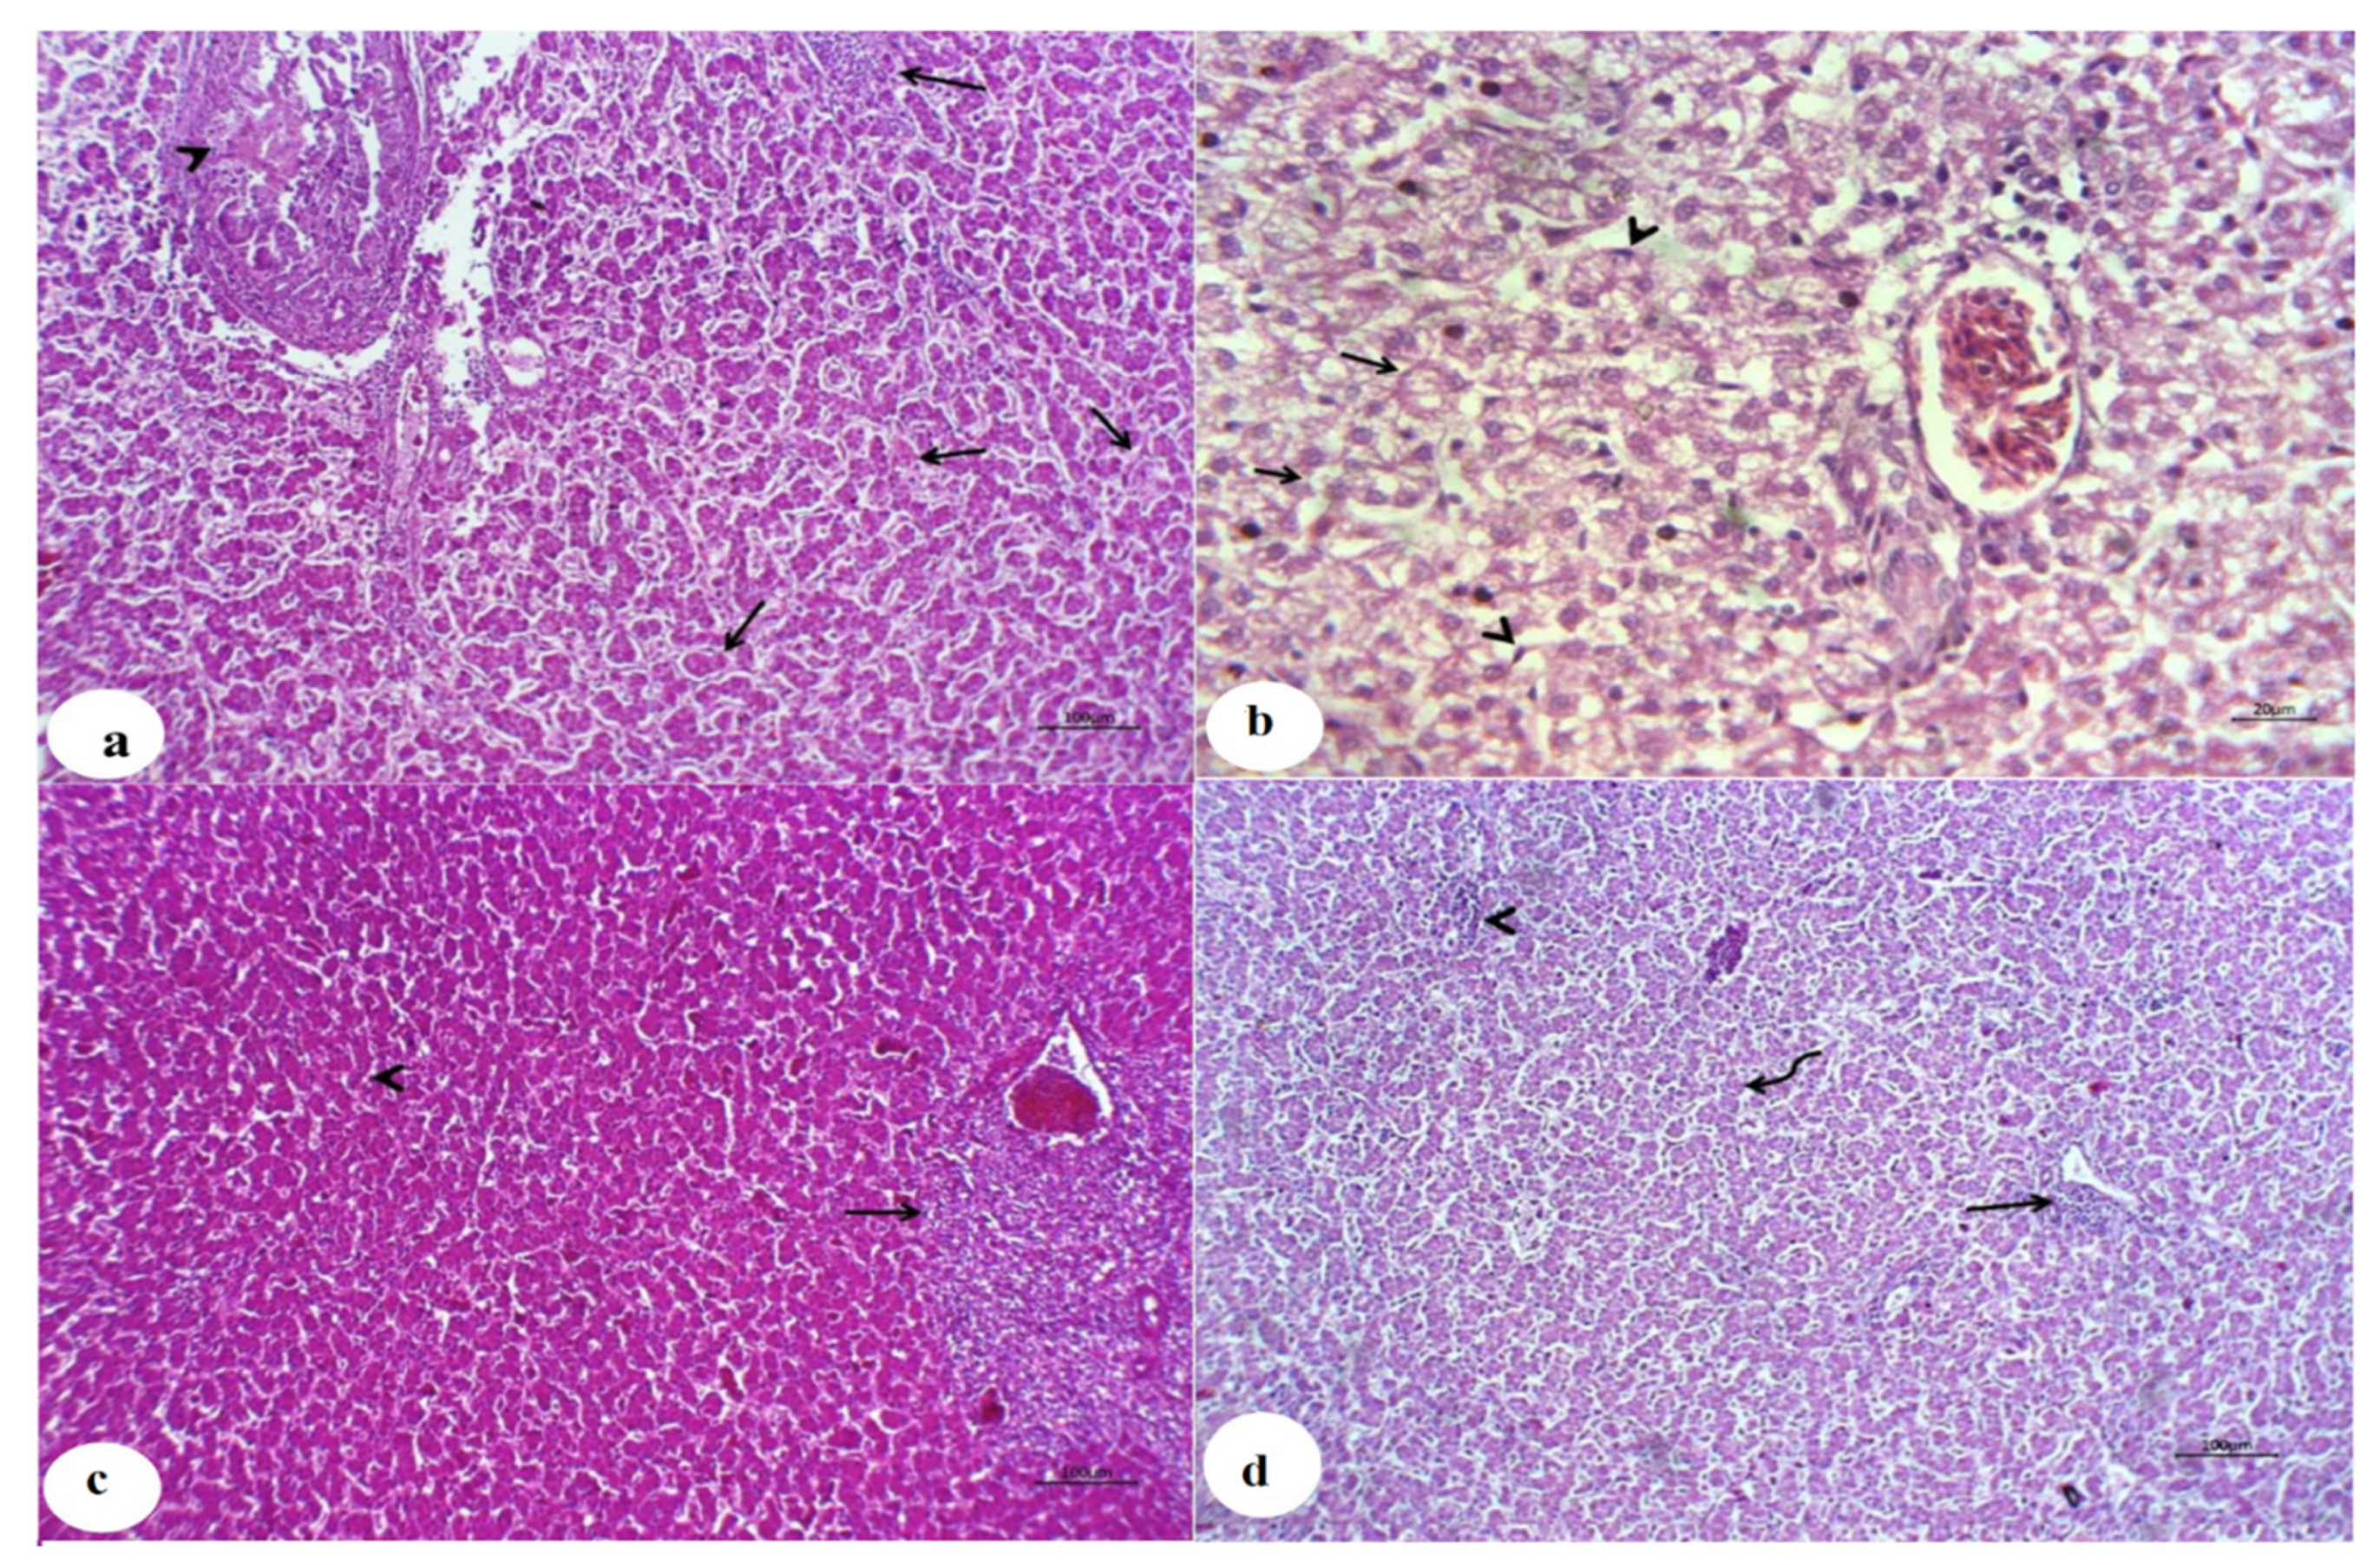

Animals Free Full Text Mitigating The Growth Biochemical Changes Genotoxic And Pathological Effects Of Copper Toxicity In Broiler Chickens By Supplementing Vitamins C And E Html